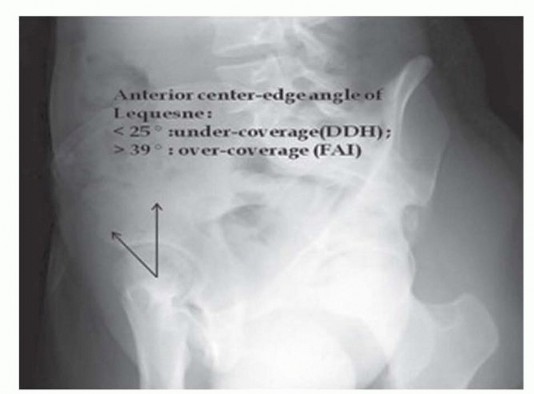

وضع لوكين (الملف الكاذب) لا يُستخدم لتشخيص الانحشار الفخذي الحقي لأنه لا يظهر العلاقة بين الجدران الحُقية الأمامية والخلفية. ومع ذلك، يُستخدم غالبًا لتشخيص التنكس المفصلي المبكر في الجزء الخلفي السفلي من الحُق، والذي يُعد موانعًا نسبية لجراحة الحفاظ على المفصل. يجب أن يُدرج وضع لوكين في التقييم الإشعاعي الشامل لاستبعاد خلل التنسج الوركي الخفيف المصاحب لأنه يبرز تغطية رأس الفخذ الأمامية (زاوية الحافة المركزية